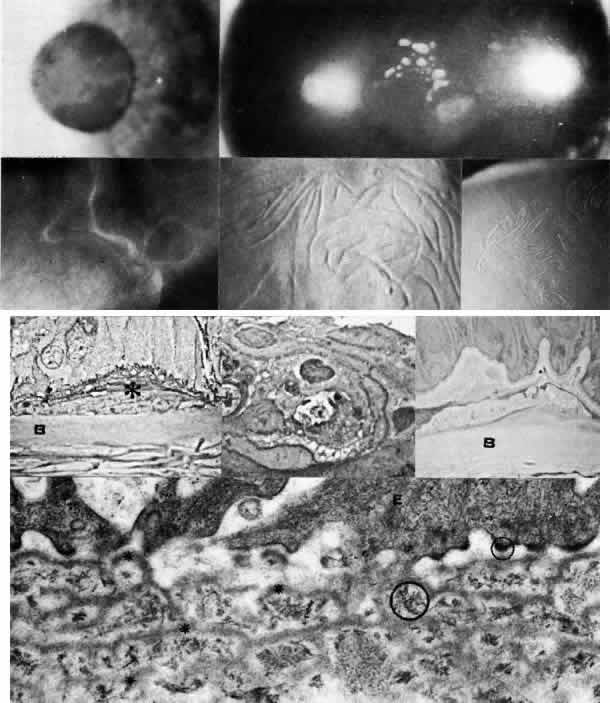

Epithelial Basement Membrane Dystrophy (Map-Dot-Fingerprint)

The appellation of map-dot-fingerprint dystrophy is appropriately descriptive of the biomicroscopically visible features of intraepithelial microcysts (dots), subepithelial ridges (fingerprints), and geographic opacities (maps) (Fig. 6; Color Plate 1D).49–66 Family studies have revealed a probable dominant inheritance for map-dot-finger-print dystrophy, with variable penetrance.67 Other clinical studies are more consistent with degeneration that is rather highly prevalent in the general population.56

Fig. 6. Map-dot-fingerprint dystrophy. Top left. Clinical photograph of a 37-year-old man with non-traumatic erosions shows characteristics of map dystrophy with superficial geographic haze interrupted by clear areas. Top right. In the dot form of Cogan's mycrocystic dystrophy, superficial, opaque cysts are evident within the epithelium. Upper middle. Three variants of fingerprint dystrophy show subepithelial ridges, particularly enhanced by retroillumination. Lower middle left. Phase-con-trast microscopy of map dystrophy shows fibrous tissue (*) interposed between epithelium and Bowman's layer (B) (paraphenylenediamine, × 1000). Lower middle center. Phase-contrast microscopy of dot dystrophy shows an intraepithelial pseudocyst evolving from disintegration of desquamating cells (paraphenylenediamine, × 1200). Lower middle right. Phase-contrast micrograph of fingerprint dystrophy illustrates fingerlike intraepithelial extensions of aberrant fibrocellular material anterior to the normal-appearing Bowman's layer (B) (paraphenylenediamine, × 800). Bottom. Transmission electron micrograph in these disorders consistently finds multiple laminations of basement membrane material (*) with reduced hemidesmosomes (small circle) and increased anchoring fibrils (large circle) beneath epithelium (E) (× 40,000). (Upper middle, slit lamp photographs courtesy of Lawrence Hirst, MD)

Many ultrastructural studies of map-dot-finger-print dystrophy have disclosed a discontinuous multilaminar, thickened basement membrane under the abnormal epithelium.49,64,65 Sometimes this abnormal basement membrane contains an admixture of collagenous and cellular debris suggestive of prior breakdown episodes. More widespread coalescence of this subepithelial material gives the clinical maplike picture. Other configurations of aberrant basement membrane and fibrillar collagens can be found extending in ridges into the epithelial layers, thereby explaining the fingerprint pattern. Epithelial microcysts are actually pseudo-cystic collections of cellular and amorphous debris within the epithelial layer. Their shape changes with time since they are formed from entrapped cellular material deeper within the epithelium. As they travel to the surface, they may coalesce with other cysts and finally break through the surface, giving rise to an irritative episode.

The primary defect in map-dot-fingerprint dystrophy is presumably the synthesis of abnormal basement membrane and adhesion complexes by the dystrophic epithelium. Unable to form proper hemidesmosomes or anchoring fibrils, the epithelium undergoes recurrent subclinical or overt episodes of dysadhesion. This periodic “lift-off” allows debris to accumulate subepithelially, providing an even less adequate substrate on which the already abnormal basement membrane must form. Moreover, intraepithelial extensions of abnormal basement membrane and collagenous material may block the normal surface migration of maturing epithelial cells, allowing the formation of encysted collections of debris. Thus, the cycle is to a degree self-perpetuating, with primary faulty epithelial adhesion secondarily causing abnormal epithelial maturation which, in turn, exacerbates the accumulation of abnormal basement membrane and collagenous debris and leads to further worsening of epithelial adhesion. Gentle débridement of severely aberrant epithelium and, in some instances, superficial keratectomy to remove subepithelial debris is an aid to conservative therapy with lubricants, hypertonic saline ointment, patching, or bandage soft contact lens.

Lattice Dystrophy

Lattice dystrophy is an autosomal dominant condition characterized by pathognomonic, branching “pipestem” lattice figures within the stroma (Figs. 5 AND 10; Color Plate 1G). Symptoms usually begin in the first decade of life and include decreased vision as well as recurrent erosions because of subepithelial and stromal accumulations of amyloid material. In time, the condition progresses to involve marked opacification of the axial stroma, as well as in the superficial layers, leaving the limbus relatively free. At this stage, since the cornea also shows a superficial haze, it becomes difficult to visualize typical lattice lesions, and hence examination of younger affected family members is useful. Amyloid accumulation under the epithelium gives rise to poor epithelial-stromal adhesion with consequent recurrent erosion syndrome.49 The dystrophy advances inexorably, and by age 40 or earlier these problems become markedly aggravated, causing considerable discomfort and visual incapacity.

Fig. 10. Lattice corneal dystrophy. Top. Slit lamp photograph demonstrates pathognomonic branching lattice figures throughout the stroma. Middle left. Phase-contrast photomicrograph shows subepithelial accumulations of fibrillar amyloid deposits (*) causing distortion of epithelial contour. B, Bowman's layer (paraphenylenediamine, × 800). Middle right. Transmission electron micrograph of basement membrane complexes reveals basement membrane irregularity and discontinuity resulting from underlying amyloid fibrils (× 21,000). Bottom left. Transmission electron micrograph of stroma shows normal collagen fibrils and keratocytes with electron-dense material abnormally dispersed extracellularly (× 16,000). Bottom right. High-magnification transmission electron micrograph resolves lattice material as masses of fine, 8- to 10-nm diameter amyloid fibrils (circled below) in comparison with larger-size stromal collagen fibrils (above) (× 75,000). (Slit lamp photographs courtesy of WJ Stark, MD)

Macular Dystrophy (Groenouw Type II)

Among the classic corneal dystrophies, macular dystrophy, unlike granular and lattice dystrophies, is an autosomal recessive disorder and is far less common. It usually begins in the first decade of life and leads to progressive visual deterioration as the stroma becomes generally cloudy, with superimposed dense, gray-white spots (Figs. 5 AND 11; Color Plate 1H). Unlike granular dystrophy, these macular spots have indefinite edges and the intervening stroma is not clear. Young patients exhibit axial lesions in the superficial layers of the cornea, but with time, lesions approach the periphery and extend throughout the entire stromal thickness. Corneal thinning confirmed by central pachymetry has been documented.129 Also unique is primary involvement of the endothelium as evidenced clinically by the presence of guttate changes of Descemet's membrane.

Fig. 11. Macular corneal dystrophy. Top left. Clinical appearance of cornea features diffuse haze extending to the limbus with superimposed, dense gray-white spots. Bottom left. Light photomicrograph of posterior cornea shows endothelial cells staining intensely positive for acid mucopolysaccharide. Guttate excrescences (*) of Descemet's membrane (DM) are frequent. The stroma also shows positive staining for acid mucopolysaccharide both diffusely extracellularly and intensely within keratocytes (circled) (colloidal iron × 500). Right. Transmission electron micrograph discloses typical fibrillary granular deposits within keratocytes (K), throughout the posterior layer of Descemet's membrane, and within the endothelial cells (En). The anterior banded region of Descemet's membrane (bracketed) is not affected (× 3500).

The lesions in macular corneal dystrophy stain intensely with alcian blue and colloidal iron, minimally with PAS, and not at all with Masson's trichrome. Birefringence is decreased. The lesions have been histochemically identified as an abnormal keratan sulfate-like glycosaminoglycan that accumulates extracellularly within the stroma and Descemet's membrane and intracellularly within keratocytes and endothelium.130

As would be typical of an autosomal recessively inherited condition, macular dystrophy presumably results from deficiency of a hydrolytic enzymes (sulfotransferase) and may thus be considered a localized mucopolysaccharidosis.131 The effect of altered glycosaminoglycan metabolism is evident at the cellular level; on transmission electron microscopy, keratocytes and endothelial cells exhibit distention of rough-surfaced endoplasmic reticulum cisternae. With the acridine orange technique, compensatory generalized hyperactivity of the lysosomal enzyme system has been demonstrated.132 Eventually the accumulated undigested storage products engorge the cells, and the cells ultimately degenerate or rupture. The derivation of these intracytoplasmic storage vacuoles from endoplasmic reticulum suggests that the biochemical lesion in macular dystrophy occurs at a different metabolic location than in the systemic mucopolysaccharidoses, since in the latter, storage products accumulate within lysosomelike intracytoplasmic vacuoles associated with the Golgi complex.133 Snip and associates134 were able to determine that the storage phenomenon affecting endothelium and Descemet's membrane is likely also primary, since the intracellular and extracellular lesions appear ultrastructurally comparable to those evident in the keratocytes and stroma.